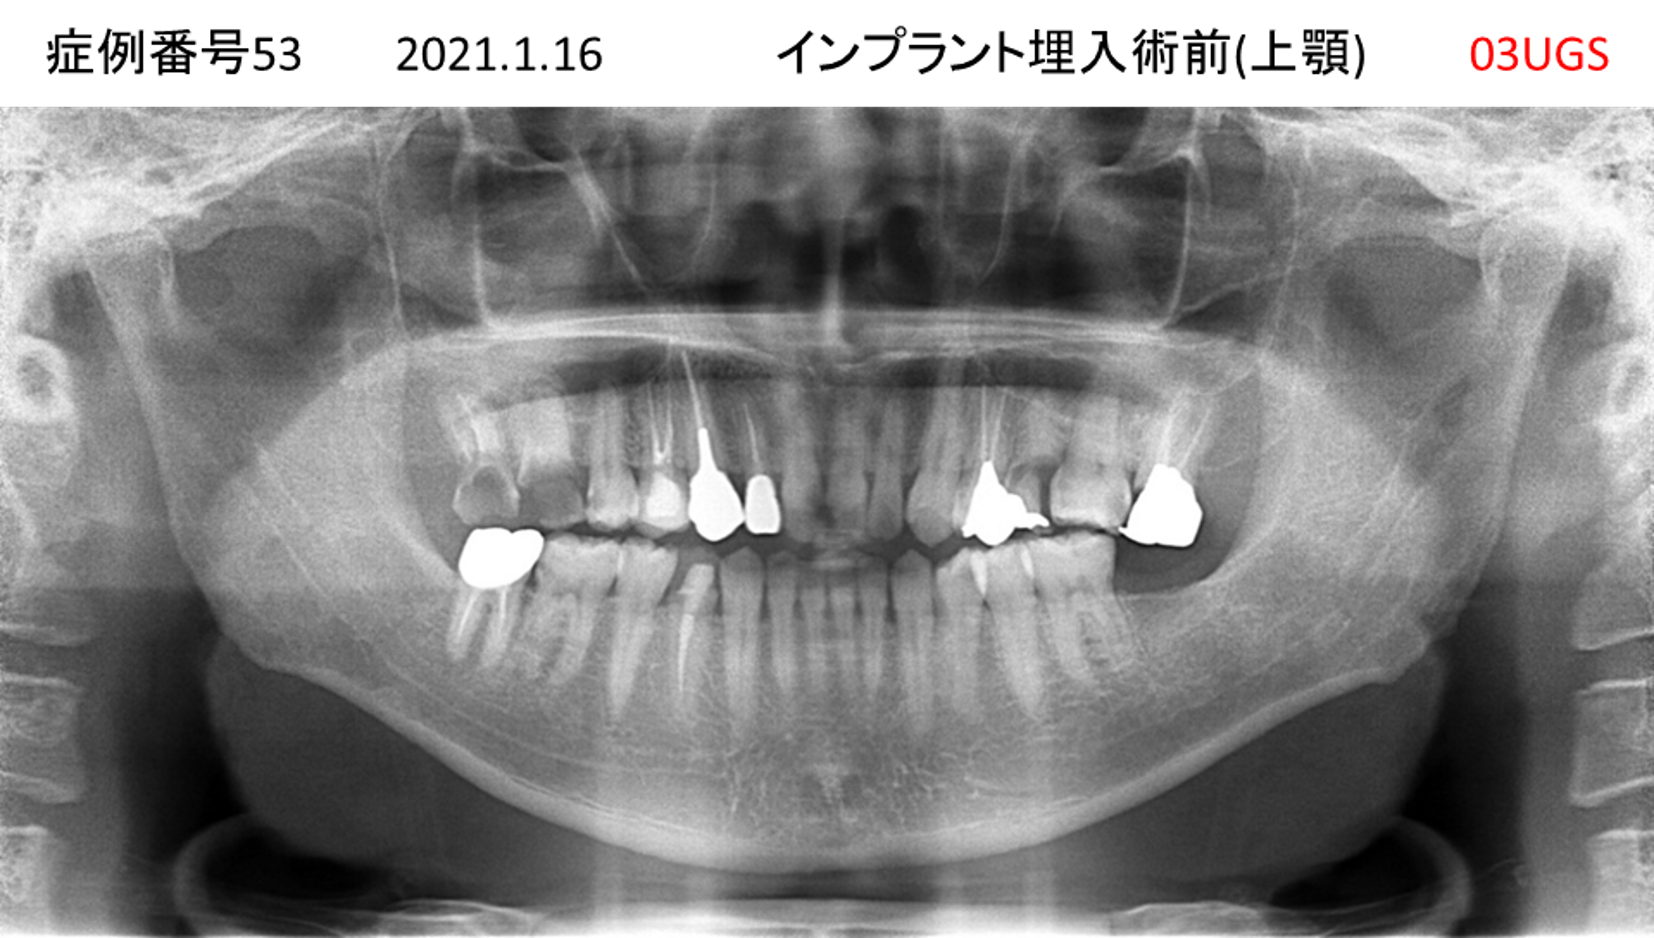

食事ができない/噛めない患者様のインプラント症例

| 治療名称 |

インプラント |

| 治療費用 |

540万円+税 |

| 治療期間 |

6か月 |

| 患者さんの症状(主訴) |

食事ができない。噛めない。上の前歯が揺れてきた。入れ歯がつらい。 |

| 治療内容 |

サイナスリフト、インプラント |

| 治療結果 |

なんでも食べられるようになった。力が入る(全身)ようになった。 |

| 治療の注意点(リスク/副作用) |

インプラントが壊れたら再治療が必要 |